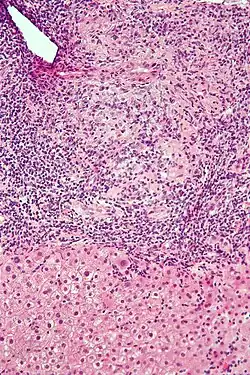

Low-magnification micrograph of PBC, H&E stain -

Intermediate-magnification micrograph of PBC showing bile duct inflammation and periductal granulomas, liver biopsy, H&E stain -

On microscopic examination of liver biopsy specimens, PBC is characterized by chronic, nonsuppurative inflammation, which surrounds and destroys interlobular and septal bile ducts. These histopathologic findings in primary biliary cholangitis include:[32]

- Inflammation of the bile ducts, characterized by intraepithelial lymphocytes

- Periductal epithelioid granulomas.

- Proliferation of bile ductules

- Fibrosis (scarring)

The Ludwig and Scheuer scoring systems have historically been used to stratify four stages of PBC, with stage 4 indicating the presence of cirrhosis. In the new system of Nakanuma, the stage of disease is based on fibrosis, bile duct loss, and features of cholestasis, i.e. deposition of orcein-positive granules, whereas the grade of necroinflammatory activity is based on cholangitis and interface hepatitis. The accumulation of orcein-positive granules occurs evenly across the PBC liver, which means that staging using the Nakanuma system is more reliable regarding sampling variability.